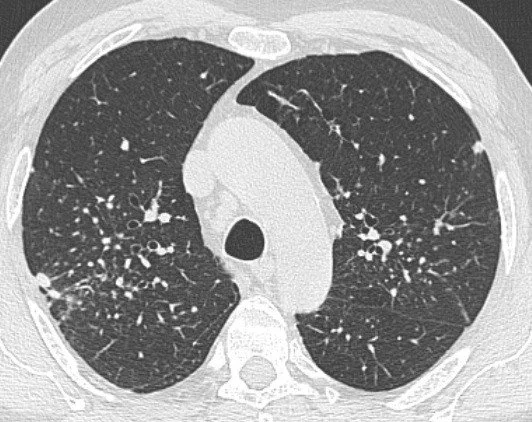

La silicose est une fibrose pulmonaire (comme l’asbestose liée à l’amiante) qui se présente sous forme de nodules fibro-hyalins (donc nettement différente de l’asbestose). Elle se caractérise au scanner par des lésions micronodulaires ou nodulaires dans le poumon. Les nodules peuvent confluer pour donner un aspect de pseudo-tumeurs.

Poumons

La silicose peut provoquer une insuffisance respiratoire chronique, dont on évalue l’importance et l’évolution à l’aide d’Epreuves Fonctionnelles Respiratoires (EFR). A terme le poumon est incapable d’apporter assez d’oxygène au sang, nécessitant alors une oxygénothérapie.

L’évolution est suivie par la pratique régulière de scanners associée à des EFR, cette démarche permettant de réévaluer si nécessaire le taux d’IPP (Incapacité permanente partielle).